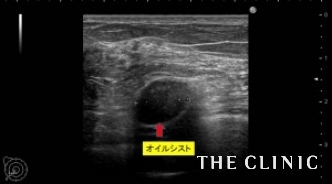

自覚されているしこりは4個でしたが、エコーではオイルシストは約20個、充実性のしこりは2個認めました。

オイルシストは、壊死した脂肪がオイル状になったものですので、注射針で吸引可能です。